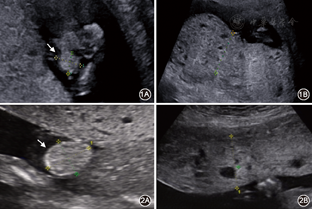

孕妇29岁,孕3产0,因"停经13周,外院超声发现胎儿脐膨出"于广东省妇幼保健院就诊,在本院复查超声示胎儿头臀长68 mm,颈项透明层厚度1.7 mm,脐膨出,胎盘增厚,内可见多个细小无回声区(图1)。夫妇双方既往体健,非近亲,否认家族遗传病史。孕妇初婚,此为第3次自然妊娠。2016年第1次妊娠,孕18周超声发现胎儿脐膨出、胎盘增厚、内见多个小无回声区(图2),诊断"不完全性葡萄胎"于孕20周引产,引产胎儿未行遗传学相关检查;个人原因人工流产1次,见家系图(图3)。为明确病因,拟对本例胎儿行遗传学检测。